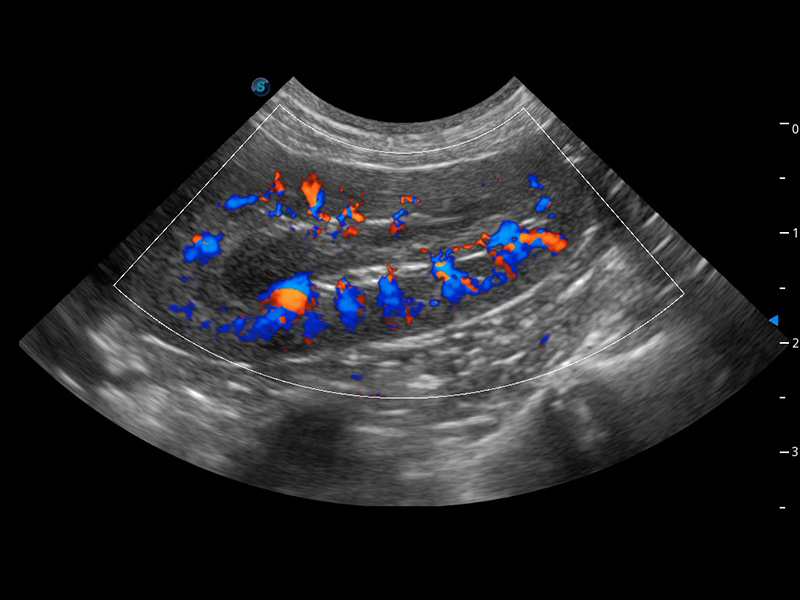

ProPet 60 作为一款高端台式动物超声设备,为动物医生的日常诊断提供了一系列贴合动物临床需求、解决临床实际问题的高级成像功能。凭借全系列高清探头,满足医生对腹部、心脏、生殖、浅表、肌骨等成像的所有需求,切实帮助您提升检查效率,提高诊断信心。

动物是人类最亲密的朋友和最值得信赖的伙伴。银河优越会也一直致力于探索动物专用的超声影像解决方案。 全新推出的ProPet系列,是银河优越会在动物超声影像智能化、专业化、精准化的一次跨越式革新。动物不能用言语来表述自己的不适,通过超声影像,ProPet系列搭建了动物医生与不同物种沟通的“桥梁”,为动物医生注入了“治愈之力”。